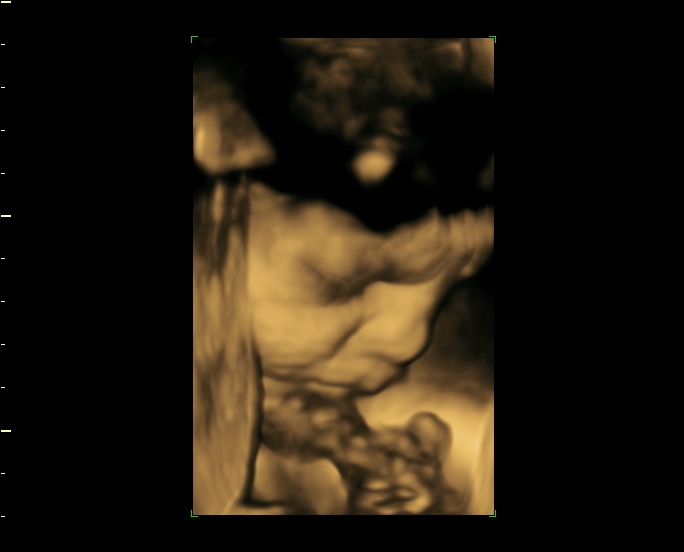

3d 4d Ultrasound At 34 Weeks

3d 4d ultrasound at 34 weeks. 34 week 3d ultrasound. 34 week pregnancy update 3d 4d ultrasound sneak peek pics duration. Medical pregnancy scans ivf fertility scans 86609 views. However we do recommend a gestational age of 26 34 weeks for the best facial detail.

Caitlyn sny 9703 views. At this stage the baby has put on some weight and filled out to make features more visible yet still enough fluid in front of babys face to obtain great images 38 weeks. 3d 5d ultrasound images and 4d ultrasound video can be obtained at any stage. Hd ultrasound appointment 146530 views.